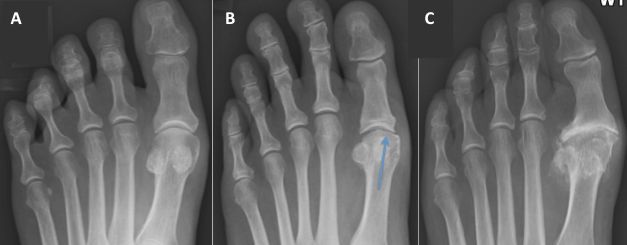

• Chirurgia del piede

• Ortopedia del piede